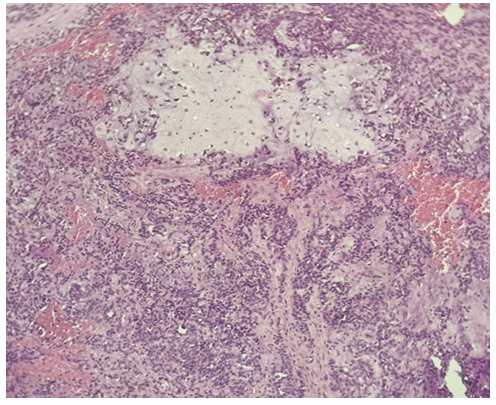

| Picture 3. Surgically resected specimen of salivary gland tumor. Histological appearance of monomorphic adenoma, localized in the left submandibular gland (1 case; No. 1101). The lesion shows uniform epithelial cell proliferation arranged in solid and trabecular patterns with sharp demarcation from the surrounding tissue (H&E stain) |

Morphological description: The histological section demonstrates infiltrative tumor growth with dense sheets of atypical epithelial cells. Cells display pleomorphism, irregular nuclear contours, hyperchromasia, and scant cytoplasm. The stroma is fibrous, with focal desmoplastic reaction. No signs of glandular or squamous differentiation are present, which is consistent with the diagnosis of undifferentiated carcinoma of the mandible. Figure 2. Undifferentiated carcinoma of the mandible showing sheets of pleomorphic tumor cells with hyperchromatic nuclei and fibrous stromal reaction. No evidence of glandular or squamous differentiation is observed (H&E stain, ×10). | Figure 3. Monomorphic adenoma (left submandibular gland, H&E stain, ×20) |

Morphological description: The section reveals a well-circumscribed salivary gland neoplasm composed of uniform epithelial cells with round to oval nuclei and scant cytoplasm. The tumor grows in a solid and trabecular pattern with minimal cellular pleomorphism. Adipose tissue infiltration is seen at the periphery, but the neoplasm maintains a distinct border from surrounding structures. No chondromyxoid stroma or mixed tissue elements are identified, which distinguishes this tumor from pleomorphic adenoma. Figure 3. Histological section of monomorphic adenoma of the submandibular gland showing uniform epithelial cells arranged in solid and trabecular patterns with sharp demarcation from adjacent adipose tissue. No stromal heterogeneity is observed (H&E stain, ×20). | Figure 4a. Pleomorphic adenoma |